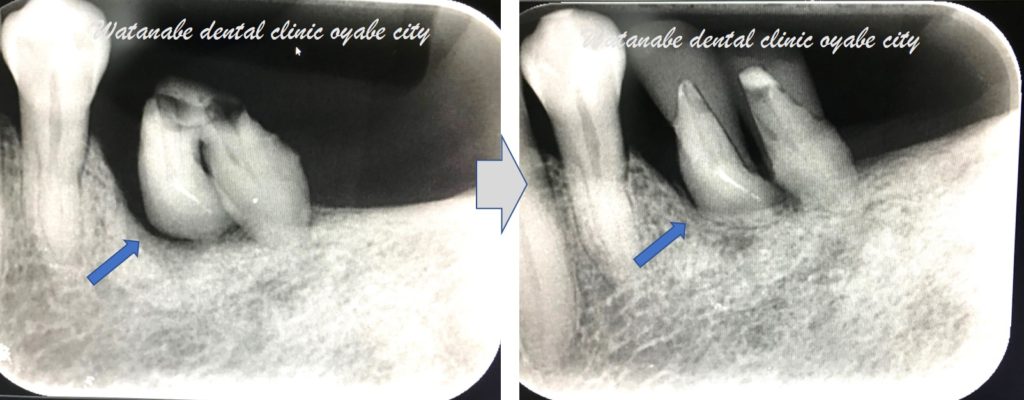

下写真は経過です。

左が術前、右が術後(6カ月後)です。

移植後も良好に経過しています。

青矢印部分の黒い影がなくなり、骨が形成されているのが確認できます。